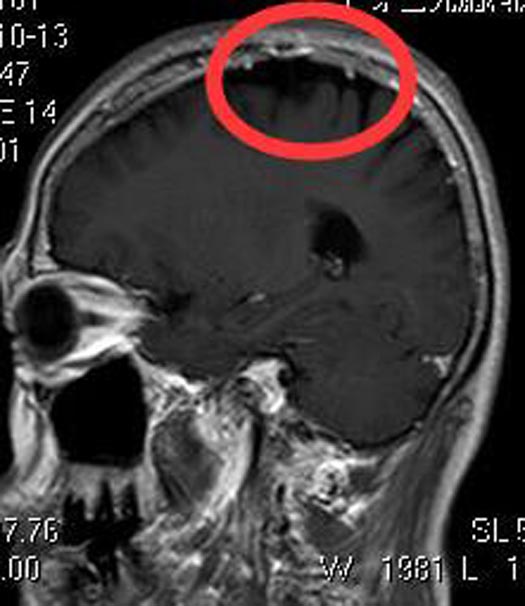

由于肿瘤血供丰富,为保障手术质量,术前予肿瘤部分供血血管栓塞,后由鲁明主任主刀,在全麻下行左额顶脑膜瘤切除术。导航定位肿瘤位置,术中见肿瘤呈烂鱼肉状,质软,有陈旧性出血,边界较清,显微镜下顺利全切肿瘤。术后病理结果提示:微囊型脑膜瘤 WHO I级。

▲术后